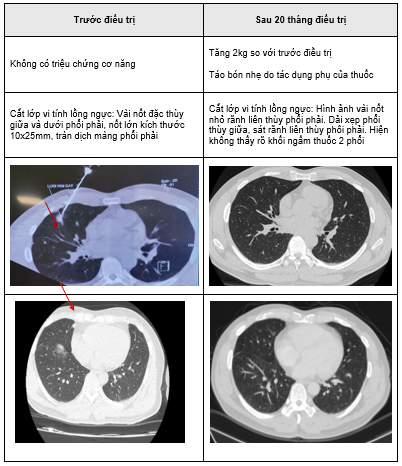

Trong quá trình dùng thuốc bệnh nhân được xét nghiệm công thức máu, sinh hoá máu, chất chỉ điểm u 1 tháng 1 lần. Chụp cắt lớp vi tính lồng ngực và cắt lớp vi tính ổ bụng 3 tháng 1 lần. Các triệu chứng lâm sàng gần như không còn, thể trạng bệnh nhân ngày càng tốt lên, chất lượng cuộc sống được cải thiện.

Chụp cắt lớp vi tính lồng ngực: Hình ảnh các nốt kính mờ rãnh liên thùy và màng phổi phải kích thước 2x3mm. Đám dải xẹp phổi thùy giữa phổi phải

Hình 6: Hình ảnh chụp cắt lớp vi tính lồng ngực: nốt tổn thương u phổi phải nhỏ hơn ban đầu sau 3 tháng điều trị (mũi tên vàng)

Đánh giá: Bệnh đáp ứng 1 phần

Điều trị tiếp: Alectinib 600mg/lần x 2 lần/ngày,uống trong bữa ăn

Chụp cắt lớp vi tính lồng ngực: Hình ảnh các nốt kính mờ rãnh liên thùy và màng phổi phải.Đám dải xẹp phổi thùy giữa phổi phải

Hình 7: Hình ảnh chụp cắt lớp vi tính lồng ngực sau điều trị, tổn thương u giảm kích thước sau 6 tháng điều trị (mũi tên vàng)

Chụp cắt lớp vi tính lồng ngực: Hình ảnh các nốt kính mờ rãnh liên thùy và màng phổi phải. Đám dải xẹp phổi thùy giữa phổi phải

Hình 8: Hình ảnh chụp cắt lớp vi tính lồng ngực sau 9 tháng điều trị

Điều trị tiếp: Alectinib 600mg/lần x 2 lần/ngày, uống trong bữa ăn

Hình 9: Hình ảnh cắt lớp vi tính lồng ngực sau 15 tháng điều trị

Sau 20 tháng điều trị: đánh giá bệnh đáp ứng 1 phần. Hiện tại bệnh nhân không có triệu chứng cơ năng trên lâm sàng, tăng 2kg so với trước điều trị. Tác dụng phụ táo bón nhẹ.

Đáp ứng hình ảnh tốt, không còn tổn thương hoạt động rõ. Không xuất hiện các tổn thương mới tại phổi hay tại các cơ quan khác

Bệnh nhân tiếp tục được điều trị duy trì Alectinib 600mg/lần x 2 lần/ngày, uống trong bữa ăn.